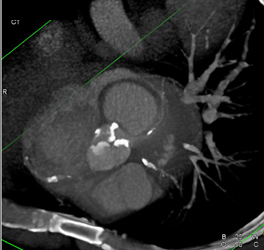

Calcified Bicuspid Valve